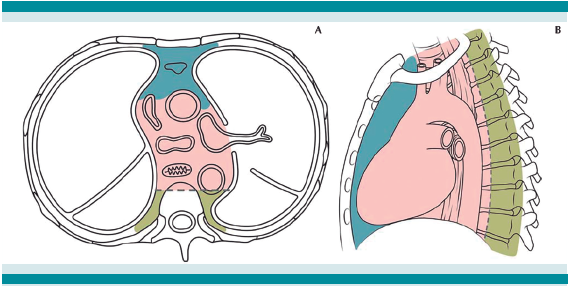

Los tumores mediastinales, de acuerdo con el tamaño y localización en los compartimentos del mediastino, se asocian con diversas manifestaciones. Algunos autores reportan pacientes asintomáticos; sin embargo, otros expresan signos y síntomas evidentes, con franca dificultad respiratoria y datos de afección vascular.2Cuadro 1

Después de ingresar al INP, la radiografía de tórax y la tomografía lograron delimitar la ubicación de la neoplasia en el segmento posterior del mediastino, de acuerdo con la taxonomía de Carter y sus colaboradores.3Figura 4

Por orden de frecuencia, los tumores de mediastino suelen aparecer en el segmento posterior en pacientes pediátricos y son los tumores neurogénicos más comunes.2,4